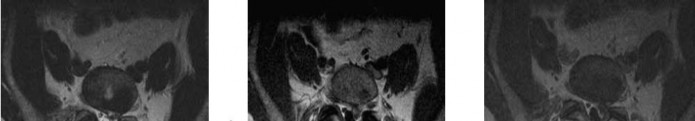

A 22-year-old male falls from a height of 30 feet. He has bilateral lower extremity weakness and perineal numbness.

Imaging demonstrates a transverse fracture through the S1-S2 level connecting bilateral longitudinal transforaminal sacral fractures (U-type fracture). What is the primary biomechanical goal of surgical fixation for this specific pattern?